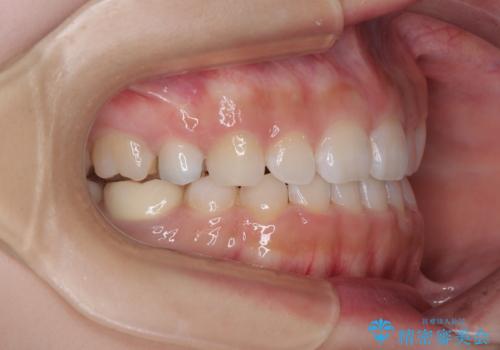

- 前歯のクロスバイトと口元の膨らんだ横顔の印象を気にして来院された患者様です。

レントゲン写真の分析結果からは、それほど口元が突出しているという結果にはなりませんでした。

しかしながら、唇を閉じたときに口元に緊張感があり、そのまま叢生を解消すると横顔が突出した印象になる可能性が高かったため、上下左右の小臼歯4本を抜歯して、ワイヤー装置にて矯正治療を行うこととしました。